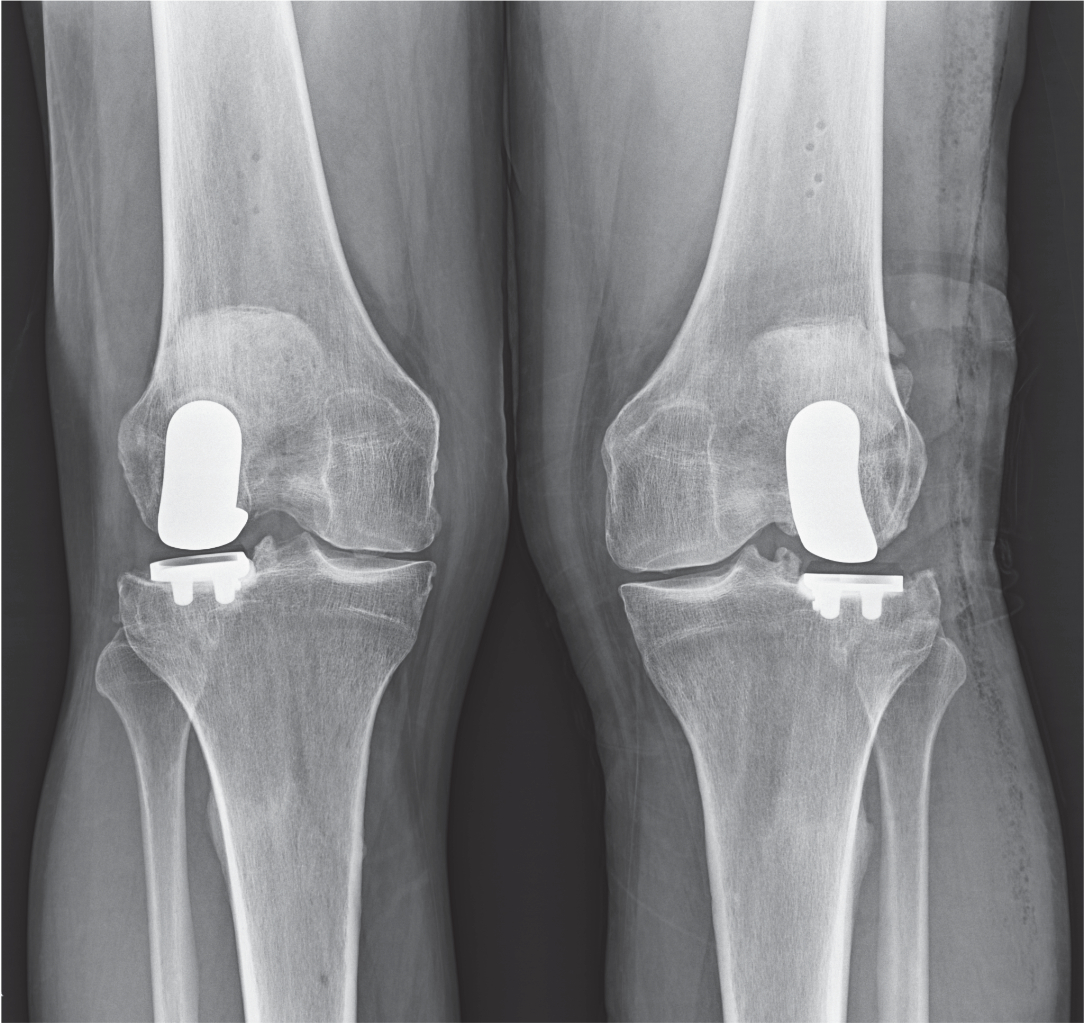

Robotic Partial Knee Surgery in robotic partial knee surgery, only the damaged portions of the knee are replaced. in robotic partial knee surgery, only the damaged portions of the knee are replaced. The knee can be divided into three areas, the medial (inside), lateral. a robotic knee replacement involves the use of a computer to generate a 3d model of your knee before using robotic systems to determine the precise. mr pai specialises in robotic partial knee replacement surgery in melbourne. A computer tomography (ct) scan of your joint is taken and used with a computer. He will ensure you have the best outcome following your robotic joint replacement. how mako robotic arm assisted partial knee replacement works. a robotic arm assisted partial knee replacement is a minimally invasive procedure for those suffering with painful.

NYC Lateral Partial Knee Replacement Robotic Partial Knee Replacement Robotic Partial Knee Surgery mr pai specialises in robotic partial knee replacement surgery in melbourne. The knee can be divided into three areas, the medial (inside), lateral. a robotic arm assisted partial knee replacement is a minimally invasive procedure for those suffering with painful. in robotic partial knee surgery, only the damaged portions of the knee are replaced. He will ensure. Robotic Partial Knee Surgery.

NYC Medial Partial Knee Replacement Robotic Partial Knee Replacement Robotic Partial Knee Surgery He will ensure you have the best outcome following your robotic joint replacement. in robotic partial knee surgery, only the damaged portions of the knee are replaced. The knee can be divided into three areas, the medial (inside), lateral. a robotic knee replacement involves the use of a computer to generate a 3d model of your knee before. Robotic Partial Knee Surgery.